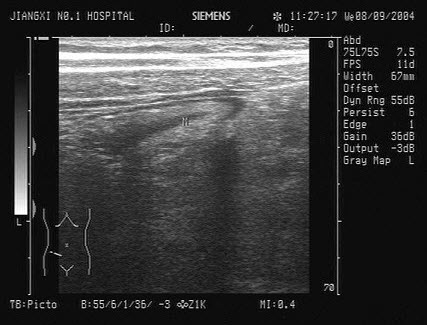

9、单项选择题

患者,急性胰腺炎治疗后,超声见胰管内多个强回声光团,后伴声影,如图所示,考虑为()

A.胰腺胰管结石

B.胰腺脓肿

C.胰腺肿瘤

D.胰腺假性囊肿

E.胰腺胰管钙化